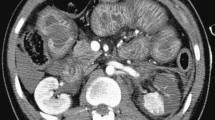

Contrast-enhanced CT in the portal venous phase, in the axial view, showing a 70-year-old male with sepsis due to gastric cancer surgery complications (qSOFA 3). In this patient, multiple CT signs of sepsis can be observed, including inferior vena cava halo sign (a, red circle), thickened bowel wall (b, white arrow), reduced enhancement, and spleen volume (c, white arrow). Figure d shows a previous CT examination of the same patient for comparison

Splenic hypoperfusion

The spleen is among the most vulnerable abdominal organs to hypotensive shock and often shows extremely decreased enhancement in early-phase CT (Figs. 2c–d). The hypoenhancement of the spleen and a reduction in the splenic volume are associated with severe hypoperfusion. The degree of hypoenhancement is believed to be directly related to hypoperfusion due to shock because the splenic artery has not autoregulatory mechanisms. Splenic hypoperfusion appears to be a useful predictor of poor prognosis among patients with systemic hypotension [23,24,25,26,27, 31].